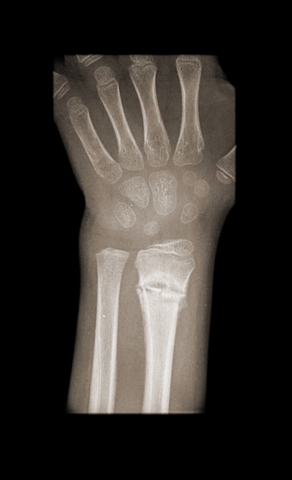

Jakaminen Sulje Röntgenkuva kädestä: sormi-, kämmen- ja ranneluut sekä kyynärluu (alh. vas.) sekä värttinäluu (alhaalla oikealla). Pysyvä osoite https://peda.net/id/H3Ltt Pysyvä tiedoston latausosoite https://peda.net/id/H3Ltt:file/download/25a9868dd38923d98657bbf58419dfc79ffe8d1b/murtunut_ranne_rongten.jpg Jakaminen muihin palveluihin Share this page to Facebook QR-koodi